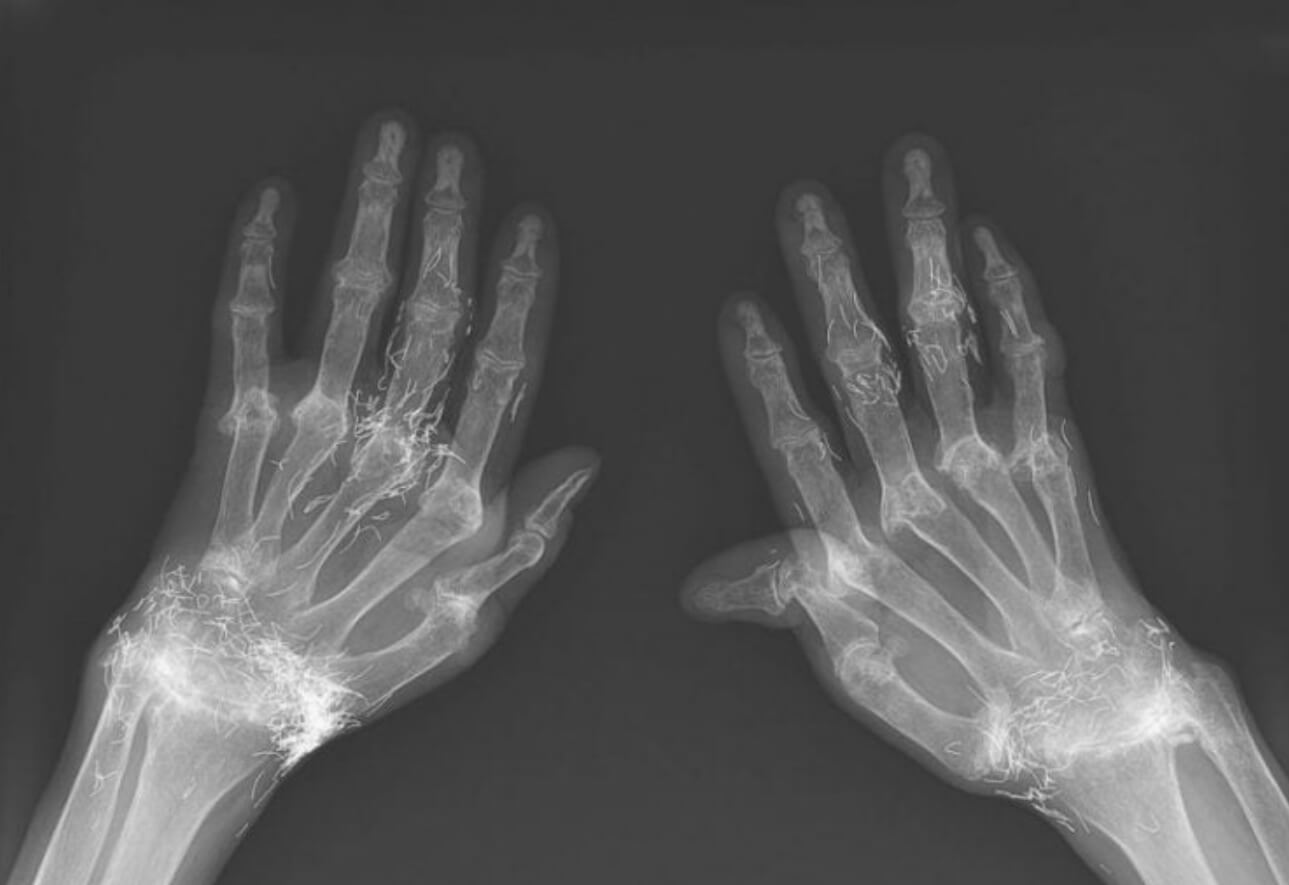

На рентгеновском снимке можно наметить крошечные нити золота. Источник изображения: The New England Journal of Medicine

Золотые нити были обнаружены даже в руках пациентки. Источник изображения: The New England Journal of Medicine

В конце концов боль стала настолько сильной, что она вернулась в больницу. Там рентген показал все сразу: классические признаки артроза и сотни золотых фрагментов, спрятанных в мягких тканях.